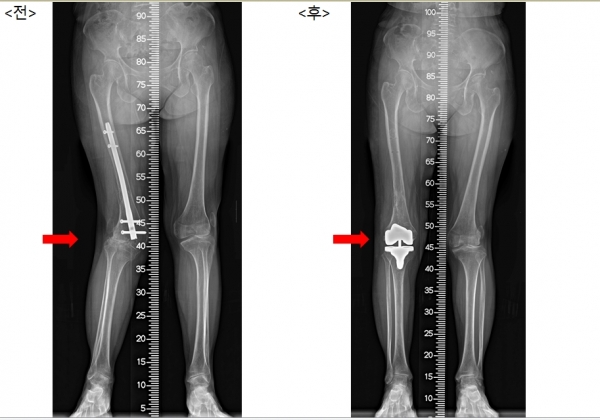

수술 전, 후 모습

김 교수는 퇴행성 변화가 나타난 관절을 절제하여 인공관절로 대체하고, 탈구된 무릎뼈를 제자리에 위치시키는 수술을 시행했다.